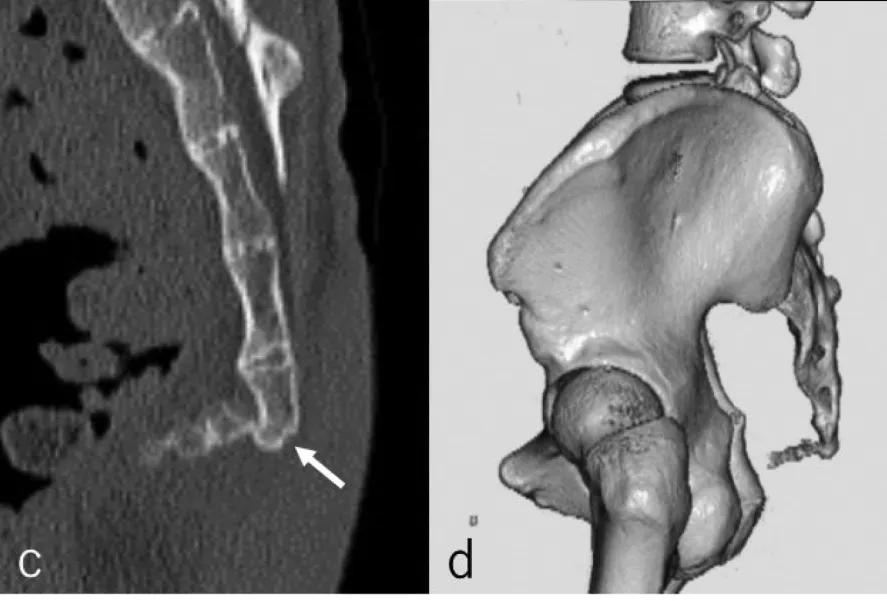

外傷(転倒や打撲による骨折・脱臼)

引用「尾骨脱臼骨折に対して受傷後早期に尾骨切除を施行した 1 例」

また、尾骨の形態や可動性も尾骨痛に関与します。過度な屈曲・伸展、側方偏位、骨棘形成などがリスクとなることが報告されています。